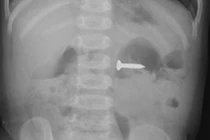

Tại Bệnh viện Nhi Trung ương, khi tiếp nhận bệnh nhi, các bác sĩ Khoa Ngoại Tiết niệu đã tiến hành các xét nghiệm cận lâm sàng và siêu âm cho bé. Kết quả siêu âm phát hiện dị vật nằm sát cổ tử cung trong âm đạo của trẻ, có cấu trúc tăng âm kèm bóng cản. Sau khi hội chẩn các bác sĩ đã quyết định nội soi âm đạo và thực hiện gắp dị vật ra khỏi âm đạo cho bệnh nhi, đó là một đồ chơi trong túi mù, kích thước 13x12mm. Sau khi được các bác sĩ lấy dị vật, tình trạng sức khỏe của trẻ ổn định và đã được xuất viện.